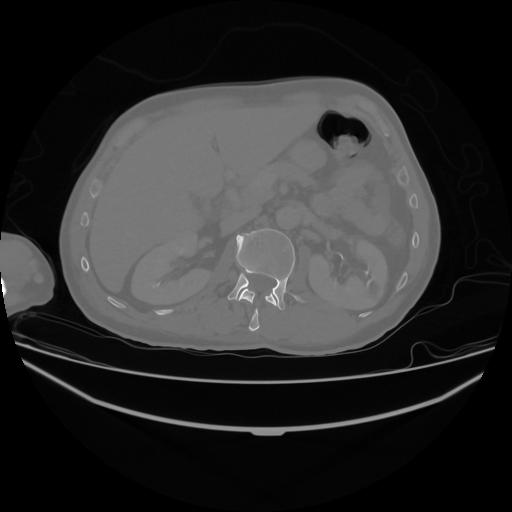

5 CUERPO,CE,Vol,1.0,CUERPO,,